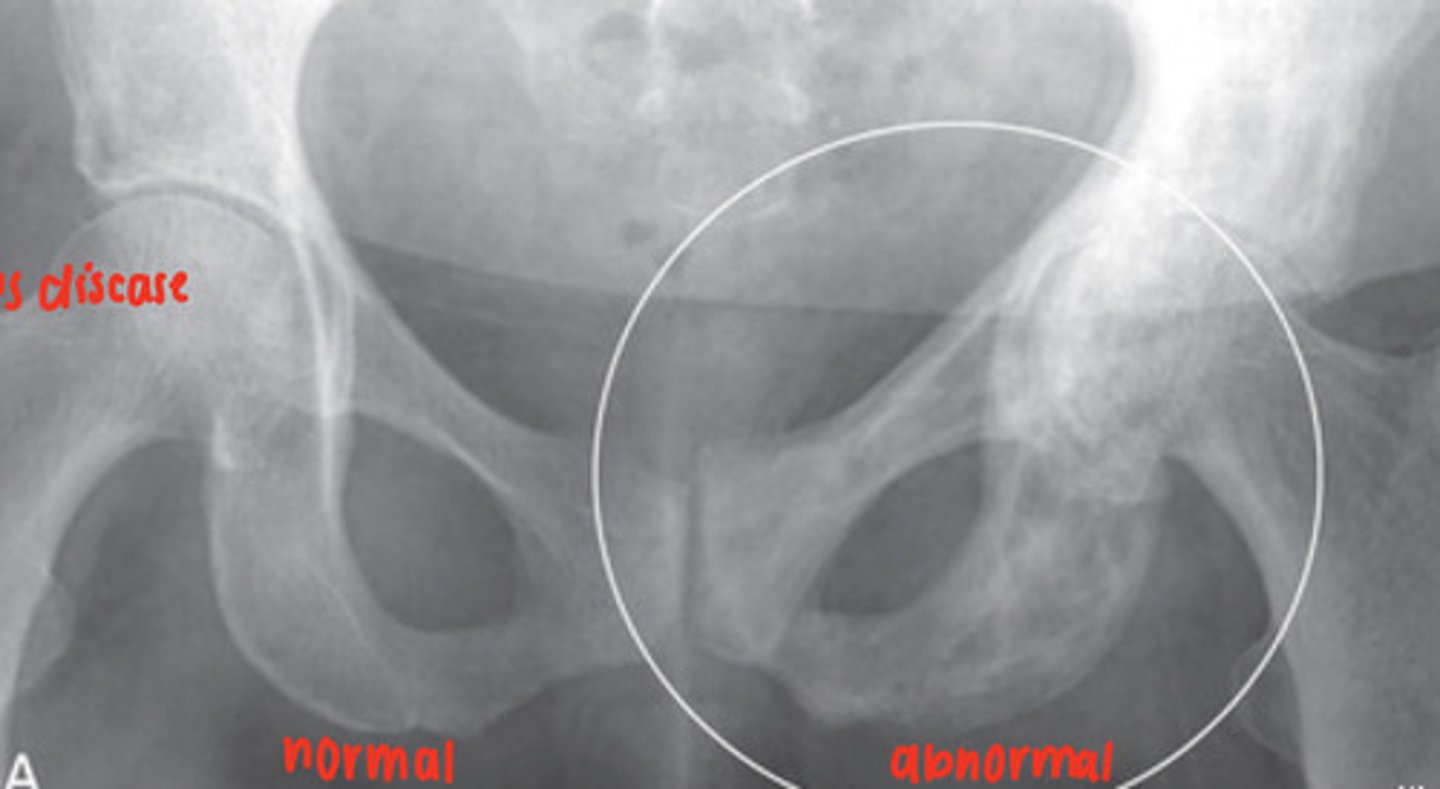

Paget's disease

focal disorder of bone metabolism, accelerated bone remodeling resulting in overgrowth, impairs integrity of affected bone, X-Ray and radionuclide bone scan